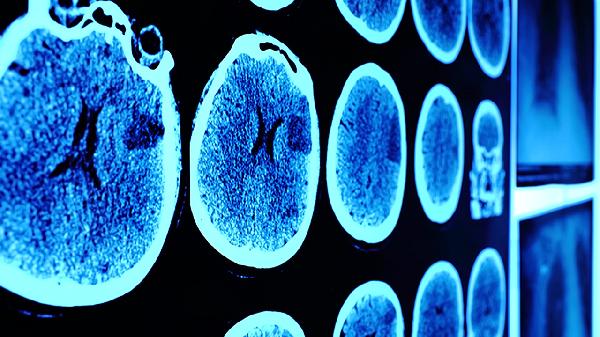

脑震荡后遗症可能包括头痛、头晕、注意力不集中、记忆力减退、睡眠障碍等症状。脑震荡通常由头部受到外力冲击引起,可能导致脑功能暂时性障碍。若出现上述症状,建议及时就医,通过神经影像学检查评估脑部损伤程度,并遵医嘱进行康复治疗。

脑震荡后恢复期间应保持适度休息,避免过早恢复剧烈运动或高强度脑力劳动。饮食上可增加富含欧米伽3脂肪酸的深海鱼、坚果等食物,补充B族维生素促进神经修复。若症状持续超过1个月或加重,需及时复查头颅CT或MRI排除其他颅内病变。康复训练需在专业医师指导下循序渐进进行,避免自行使用未经证实的偏方或保健品。